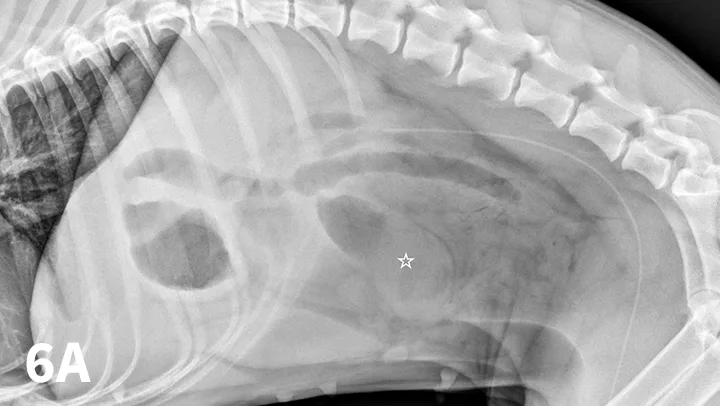

FIGURE 6A

Left lateral (A) and VD (B) survey radiographs of a 4-year-old pit bull terrier with a 3-day history of vomiting, diarrhea, and anorexia. A dilated loop of bowel is present within the midabdomen (star) caudal to the stomach, which could represent large or small bowel.